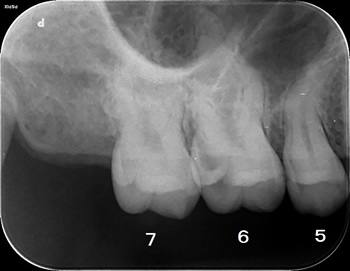

表面的には「白っぽく」なっているだけでしたが、レントゲンで確認すると、6番目の歯は「かなり大きな虫歯」で歯髄(歯の神経)にギリギリかもです!

それとやっぱり5番目の歯にも虫歯が見えますね!

このレントゲンをお見せしても、ご本人は穴があいている感じがしないのもありどうも納得されておりません!!!

んんん~、、、

その場合は、「麻酔をして少し削ってから虫歯をお見せしますので!」

と言い、、、ほっとくわけにもいかないので治療に入ります! |